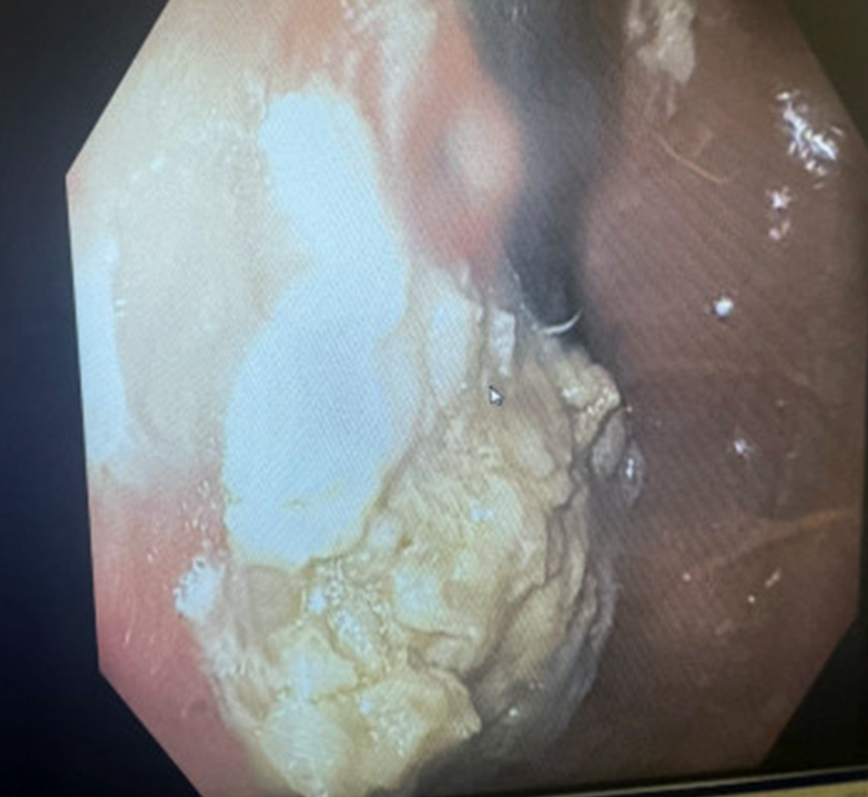

Οι γιατροί αφαίρεσαν την τσίχλα με άκαμπτη οισοφαγοσκόπηση, με τη βοήθεια ενός μεταλλικού σωλήνα και χρησιμοποιώντας λαβίδες για να πιάσουν τη μάζα.